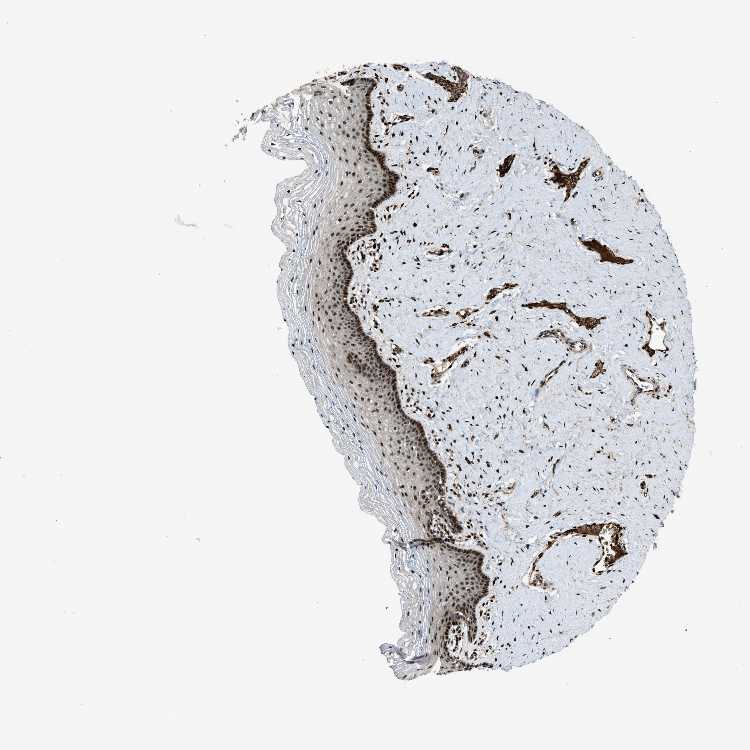

TISSUE PRIMARY DATA VAGINA Show tissue menu

VAGINA - Antibody stainingi

Antibody staining in the annotated cell types in the current human tissue is reported as not detected, low, medium, or high, based on conventional immunohistochemistry profiling in selected tissues. This score is based on the combination of the staining intensity and fraction of stained cells.

Each image is clickable and will lead to virtual microscopy that enables deeper exploration of all samples and also displays staining intensity scores, fraction scores and subcellular localization as well as patient and tissue information for each sample.

Antibody HPA021193

Squamous epithelial cells High